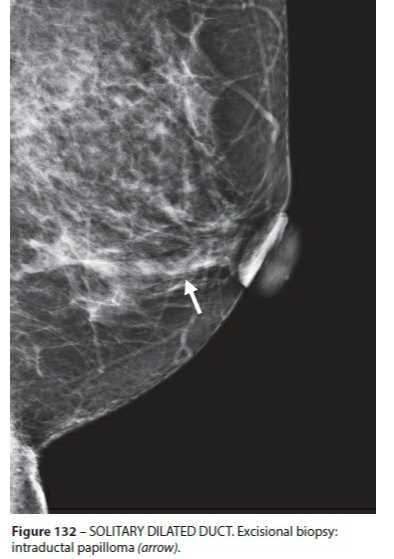

Ectasie Canlaire Solitaire

- Rare

ductal duct ectasia canal canalaire ectasiante

Ectasie Canlaire Solitaire

ductal duct ectasia canal canalaire ectasiante